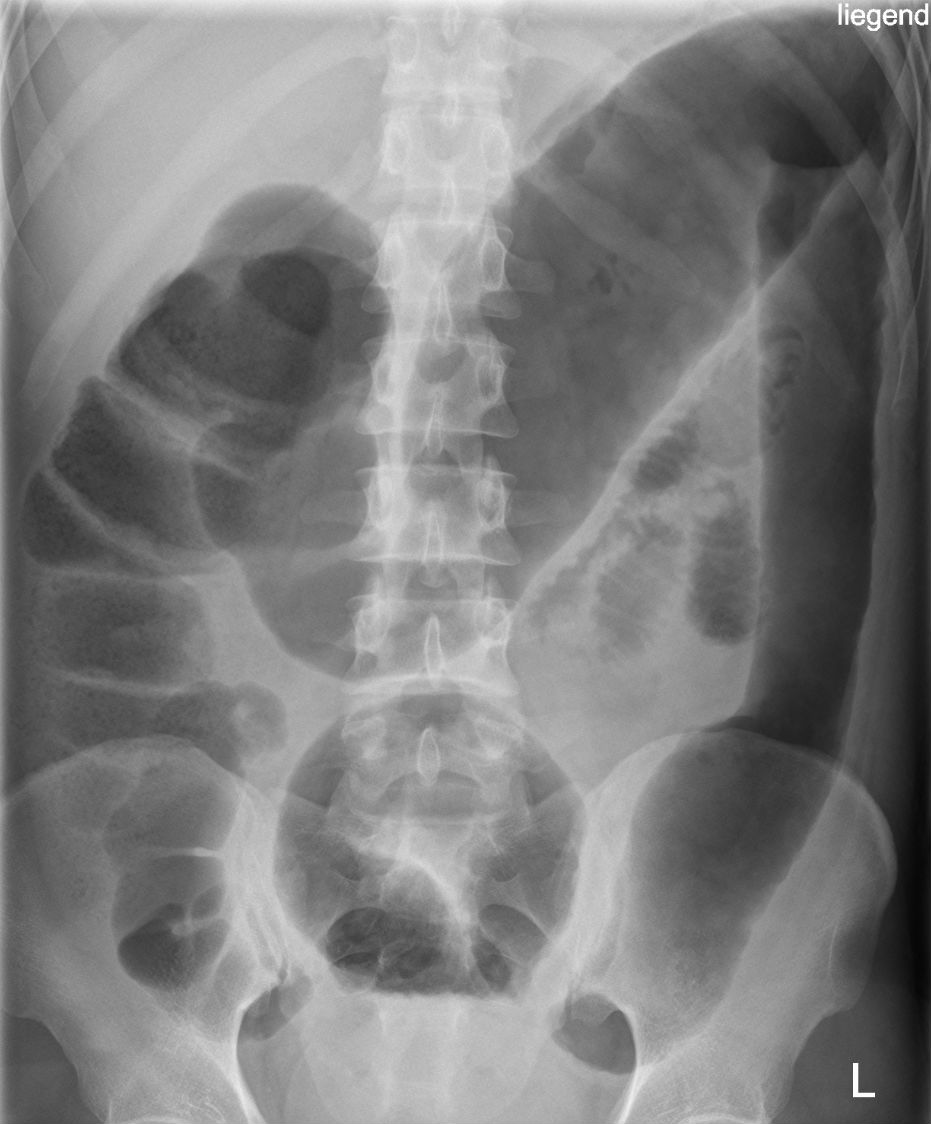

Example 5

Diagnosis

Caecal Volvulus (“embryo sign”)